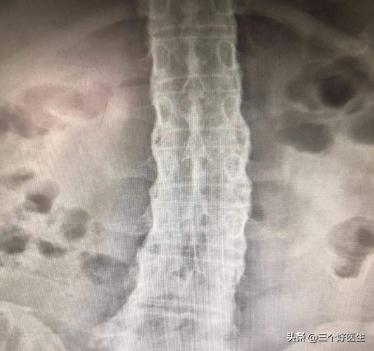

3.拍骨盆X光片显示有炎性反应,到了疾病后期X光显示脊椎关节有竹节样增生,这是本病最具有特色的表线。

X光片显示腰椎和胸椎竹节样增生